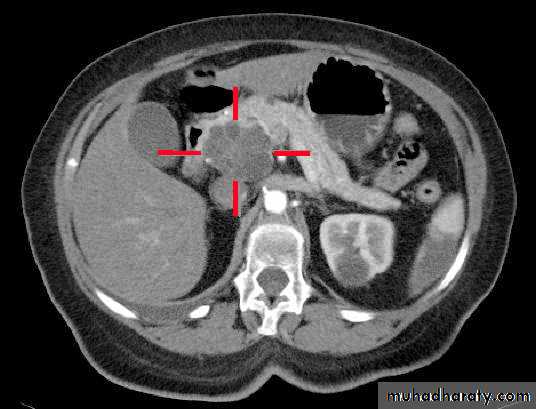

Acute Pancreatitis

CT used to

• 1. Pancreatic necrosis .• 2. An abscess.

• 3. Vascular complications.

• 4. Pseudocyst

1

3

2

4